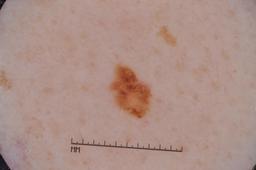

MSK-4

- Name: MSK-4

Description:

Images found based on a search for patients with a personal history, clinical diagnosis, or differential diagnosis of melanoma. All diagnoses confirmed by histopathology.